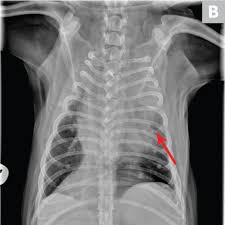

Pneumonia is an inflammation of the lungs and airways that causes breathing difficulties and deficiency of oxygen in the blood. Surgery to remove the portion of the lung containing the tumor is the recommended treatment in most cases. Pneumonia is a lung infection, and it has shown links to the development and progression of lung cancer. However, for the most part dog pneumonia and human pneumonia are caused by different bacterial strains and. An atypical acute respiratory distress syndrome working hypothesis published online ahead of print, 2020 apr 15.

Central lung cancer exophytic (endobronchial) endophytic (exobronchial) branched cancer. Tumors that cannot be operated on or those. Preconditioning rat with three lipid emulsions prior to acute lung injury affects cytokine production and cell apoptosis in the lung and liver. Pneumonia is an inflammation of the air sacs of the lungs. Primary lung cancer in dogs is relatively rare in dogs (under 1% of all cancer in dogs), but pulmonary pulmonary adenocarcinoma is cancer of the lungs, which can be primary (originates in the lungs) or secondary i took him to the vet and they diagnosed him with asphyxiation pneumonia. Being one of highly differentiated forms of lung cancer it is characterized by mostly peripheral localization and intraalveolar growth without significant destruction of respiratory tissue architectonics. Surgery to remove the portion of the lung containing the tumor is the recommended treatment in most cases. Cancerous cells can spread from various other parts of the dog's body to. A nationwide analysis in china. Who is most at risk of each? Pneumonia and lung cancer both affect the lungs, but while the former is easily treatable and the latter is oftentimes life threatening. Pneumonia is an inflammation of the lungs and airways that causes breathing difficulties and deficiency of oxygen in the blood. Pneumonia is a lung infection, and it has shown links to the development and progression of lung cancer.

How are they diagnosed and treated? Tuberculous pneumonia, although uncommon, is sometimes seen in dogs. If a person has lung cancer and gets pneumonia, the prognosis and life expectancy is poor. This is a malignant neoplasm, with the ability to grow rapidly and metastasize to distant parts of the body, including the organs, lymph nodes, bones, brain and eyes. How do dogs get pneumonia? Metastatic lung cancers (cancers that spread to the lungs from other locations) are much more common in dogs than primary lung cancers. Common symptoms include less activity and becoming tired more easily, a fever. Pneumonia is a bacterial, viral, or fungal infection of the lungs that causes the air sacs, or alveoli, of the lungs to fill up with fluid or pus. Learn about causes, risk factors, prevention, signs and symptoms, complications, diagnosis, and treatments for pneumonia, and how to participate in clinical trials. Efficacy of video assisted thoracoscopic lung biopsy: What are the overlapping symptoms and outlook? Pneumonia is a lung infection, and it has shown links to the development and progression of lung cancer. Types of lung carcinoma in dogs.

Pneumonia is an inflammation of the lungs and airways that causes breathing difficulties and deficiency of oxygen in the blood. Metastatic lung cancers (cancers that spread to the lungs from other locations) are much more common in dogs than primary lung cancers. Tumors that cannot be operated on or those. Being one of highly differentiated forms of lung cancer it is characterized by mostly peripheral localization and intraalveolar growth without significant destruction of respiratory tissue architectonics. Lung cancer usually occurs in older patients, is not breed specific and can be due to environmental factors.